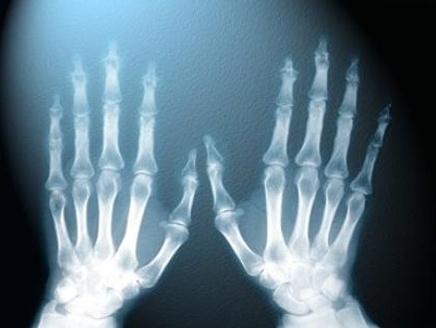

1895- صحيفة المانية تعلن ان وليام رونتغن اكتشف الاشعة السينية.